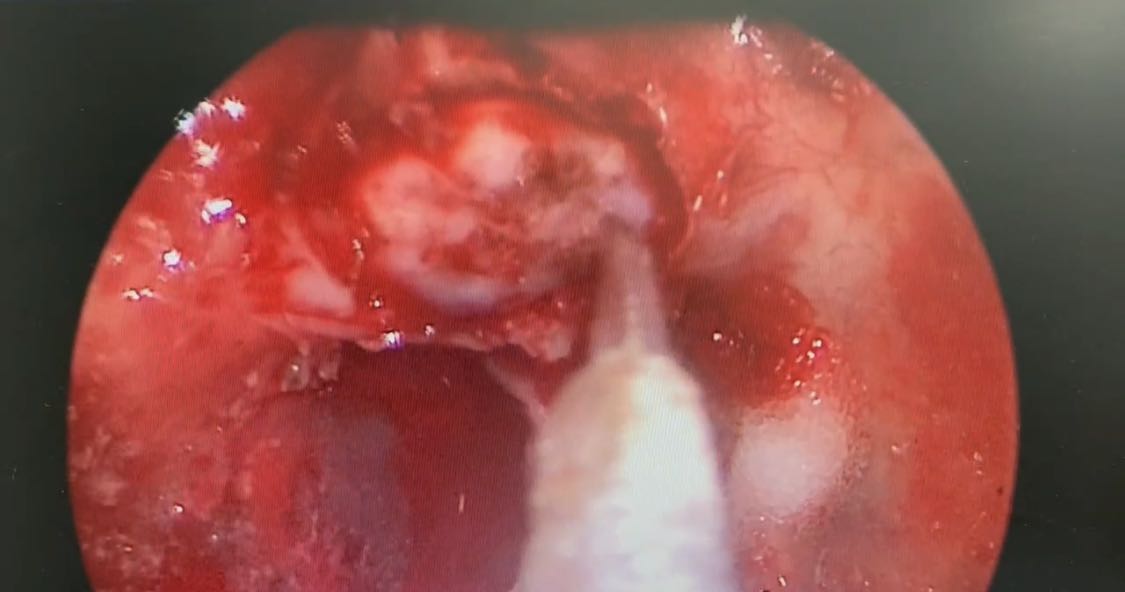

泌尿外科种铁教授团队成功完成1例复杂机器人辅助腹腔镜腹膜后副神经节瘤切除手术

8月26日,泌尿外科种铁教授团队完成1例复杂机器人援助腹腔镜下腹膜后副神经节瘤切除术。该例患者腹膜后副神经节瘤被腹主动脉、下腔静脉、肠系膜动静脉、右肾动脉、左肾静脉等7条大血管以及十二指肠、胰腺等重要脏器紧密包裹,...